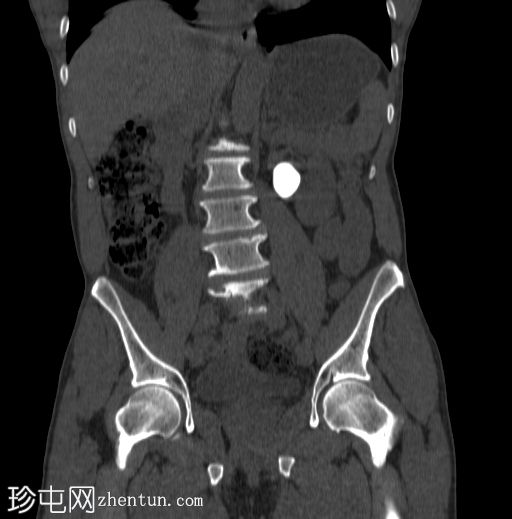

定位像

定位像显示:

左上腹象限可见一边界清晰的卵圆形不透光影